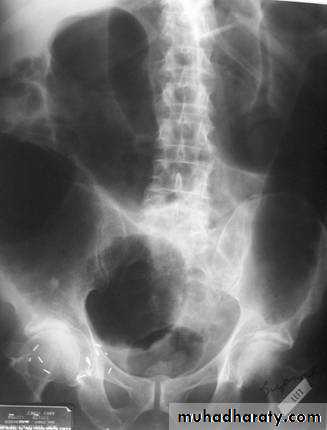

Bowel obstruction

Plain x ray SBOdilated loops with air fluid level in erect position

centrally placed

transverse lines (circular folds ) valvule convent's

Plain x ray LBO

dilated bowel with gasperipheral

haustra (not lines across bowel)

may have cut-off point